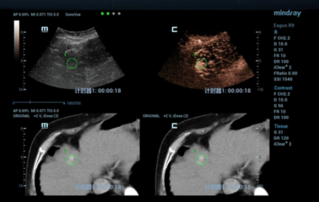

Endocavity ?? ?? ?? ???(DE10-3WU, Resona 7, Mindray)? ??? ??? ???? ?? ?? ????(Levator ani nuscle)? ??? ???. ???? ?? ??? 3~4mm? ????, ???(levator hiatus) ?? ?? - 6.13cm, LUG1(??? m ??? ??. Bulbocavernosus) ŌĆō 2.95cm ? LUG2 ŌĆō 3.15cm(?? 2.5cm ??)

??? ???? ??? ?? ????? ??? ??? ?? ?????. ????? ? ??? 30mm?? 42mm?? ??? ? ??? ??? ??? ????? ?? ? ? ?? ? ?? ? ?? ??? ??? ??? ? ????. ?? R ? ???? ?? ?? ?? ?? ?? 7mm, ?? ?? 8mm???.